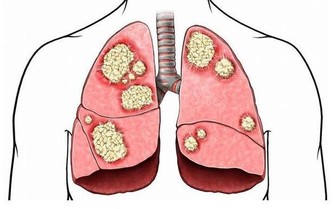

惡性黑色素瘤是皮膚癌的一種,雖然在中國還不是很常見,但是在歐美地區卻是常見的惡性腫瘤之一。在我國不常見並不意味著黑痣對人體是無害的,近幾年來皮膚癌在我國的發病率也逐漸升高,所以我們還是需要了解其產生的原因,事先做好防護措施,防患於未然。 為什麼說腳趾上的黑痣更容易演變成癌症因子呢?因為黑痣在正常情況下癌變的機率是比較小的,但是如果經常遇到摩擦、擠壓,將會增大其癌變的可能性。我們的腳趾常年處於摩擦和擠壓的狀態下,所以更加容易造成癌變。 黑痣本身就是我們身體與生俱來的良性腫瘤。後天由於生活環境的影響以及自身各個器官的病變,導致了其進一步惡化為黑色素瘤。 還有一部分認為,黑痣只有在暴曬的情況下才會演變成黑色素瘤,但是我們正常情況下是不會暴曬到腳趾部位的。所以我們會容易忽略掉腳趾上的「癌症病毒」。但是,作為皮膚癌中最危險的黑色素瘤,是非常容易發展到不經常接觸陽光的部位。黑素瘤甚至可能出現在腳趾甲下面,看起來就像是一個普通的黑點。 所以如果腳趾部位出現黑痣的話,請大家要做好保護措施,經常觀察黑痣是否有異常變化,如果出現異常請儘快就醫。 3、勺子狀的腳指甲 有時對指甲的傷害或是長期接觸石油基質溶劑可能造成凹陷的像勺子一樣的腳趾形狀。同時,缺鐵也可能會形成這種特殊形狀。